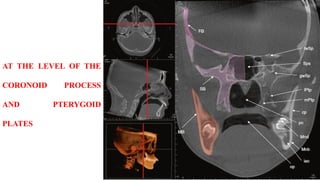

AT THE LEVEL OF THE

CORONOID PROCESS

AND PTERYGOID

PLATES

AT THE LEVELOF THE CORONOID PROCESS AND PTERYGOID PLATES